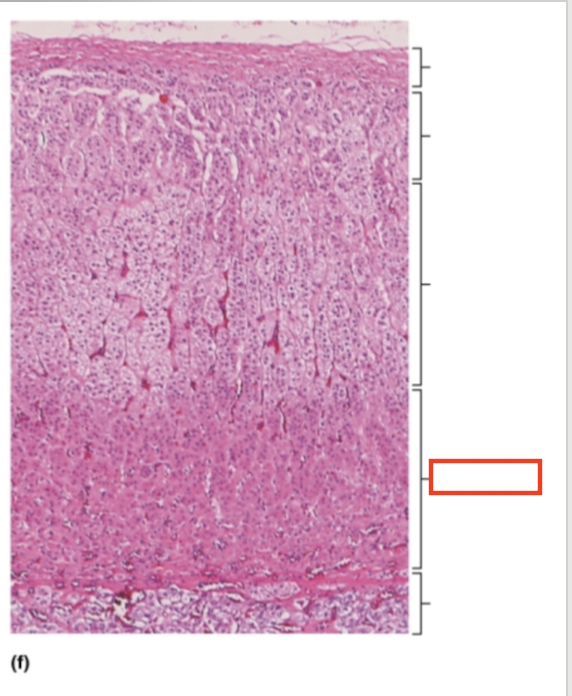

What structure is highlighted?

capsule

What structure is highlighted?

zona glomerulosa

What structure is highlighted?

zona fasciculata

What structure is highlighted?

zona reticularis

What structure is highlighted?

adrenal medulla

What tissue is shown?

adrenal gland